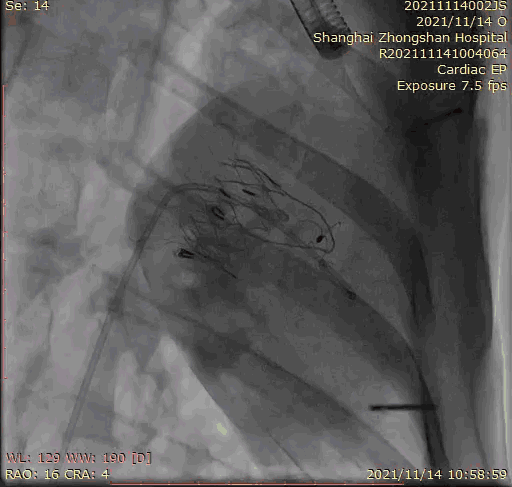

本次臨床前研究經(jīng)右側(cè)頸靜脈置入LuX-Valve Plus輸送系統(tǒng)可調(diào)彎鞘管,在DSA及超聲引導下將人工三尖瓣瓣膜植入到原有三尖瓣位置,利用獨特的錨定技術(shù)將人工瓣膜支架可靠固定在預(yù)定的位置。

上海中山醫(yī)院葛均波院士、錢菊英院長、周達新教授、潘文志教授、潘翠珍教授、李偉教授共同完成此次臨床前研究。術(shù)后葛均波院士對Lux-Valve Plus的器械操作性能給予了高度評價,DSA和超聲影像也顯示出在本次研究中Lux-Valve Plus的安全性和有效性俱佳。